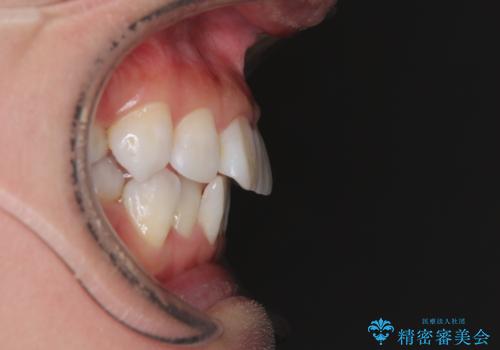

- 上下前歯の後戻りを気にして来院された患者様です。

インビザラインでの治療を希望されていて、デコボコの程度が中等度であり、安価なパッケージにて対応可能と判断されたため、インビザライン・モデレートを用いて矯正治療を行うこととしました。

インビザライン・モデレートは、製作できるアライナーの枚数に制限があるため、移動可能な量に限りがあるものの、インビザライン・ライトよりも枚数が多いため、幅広い症例に対応可能です。